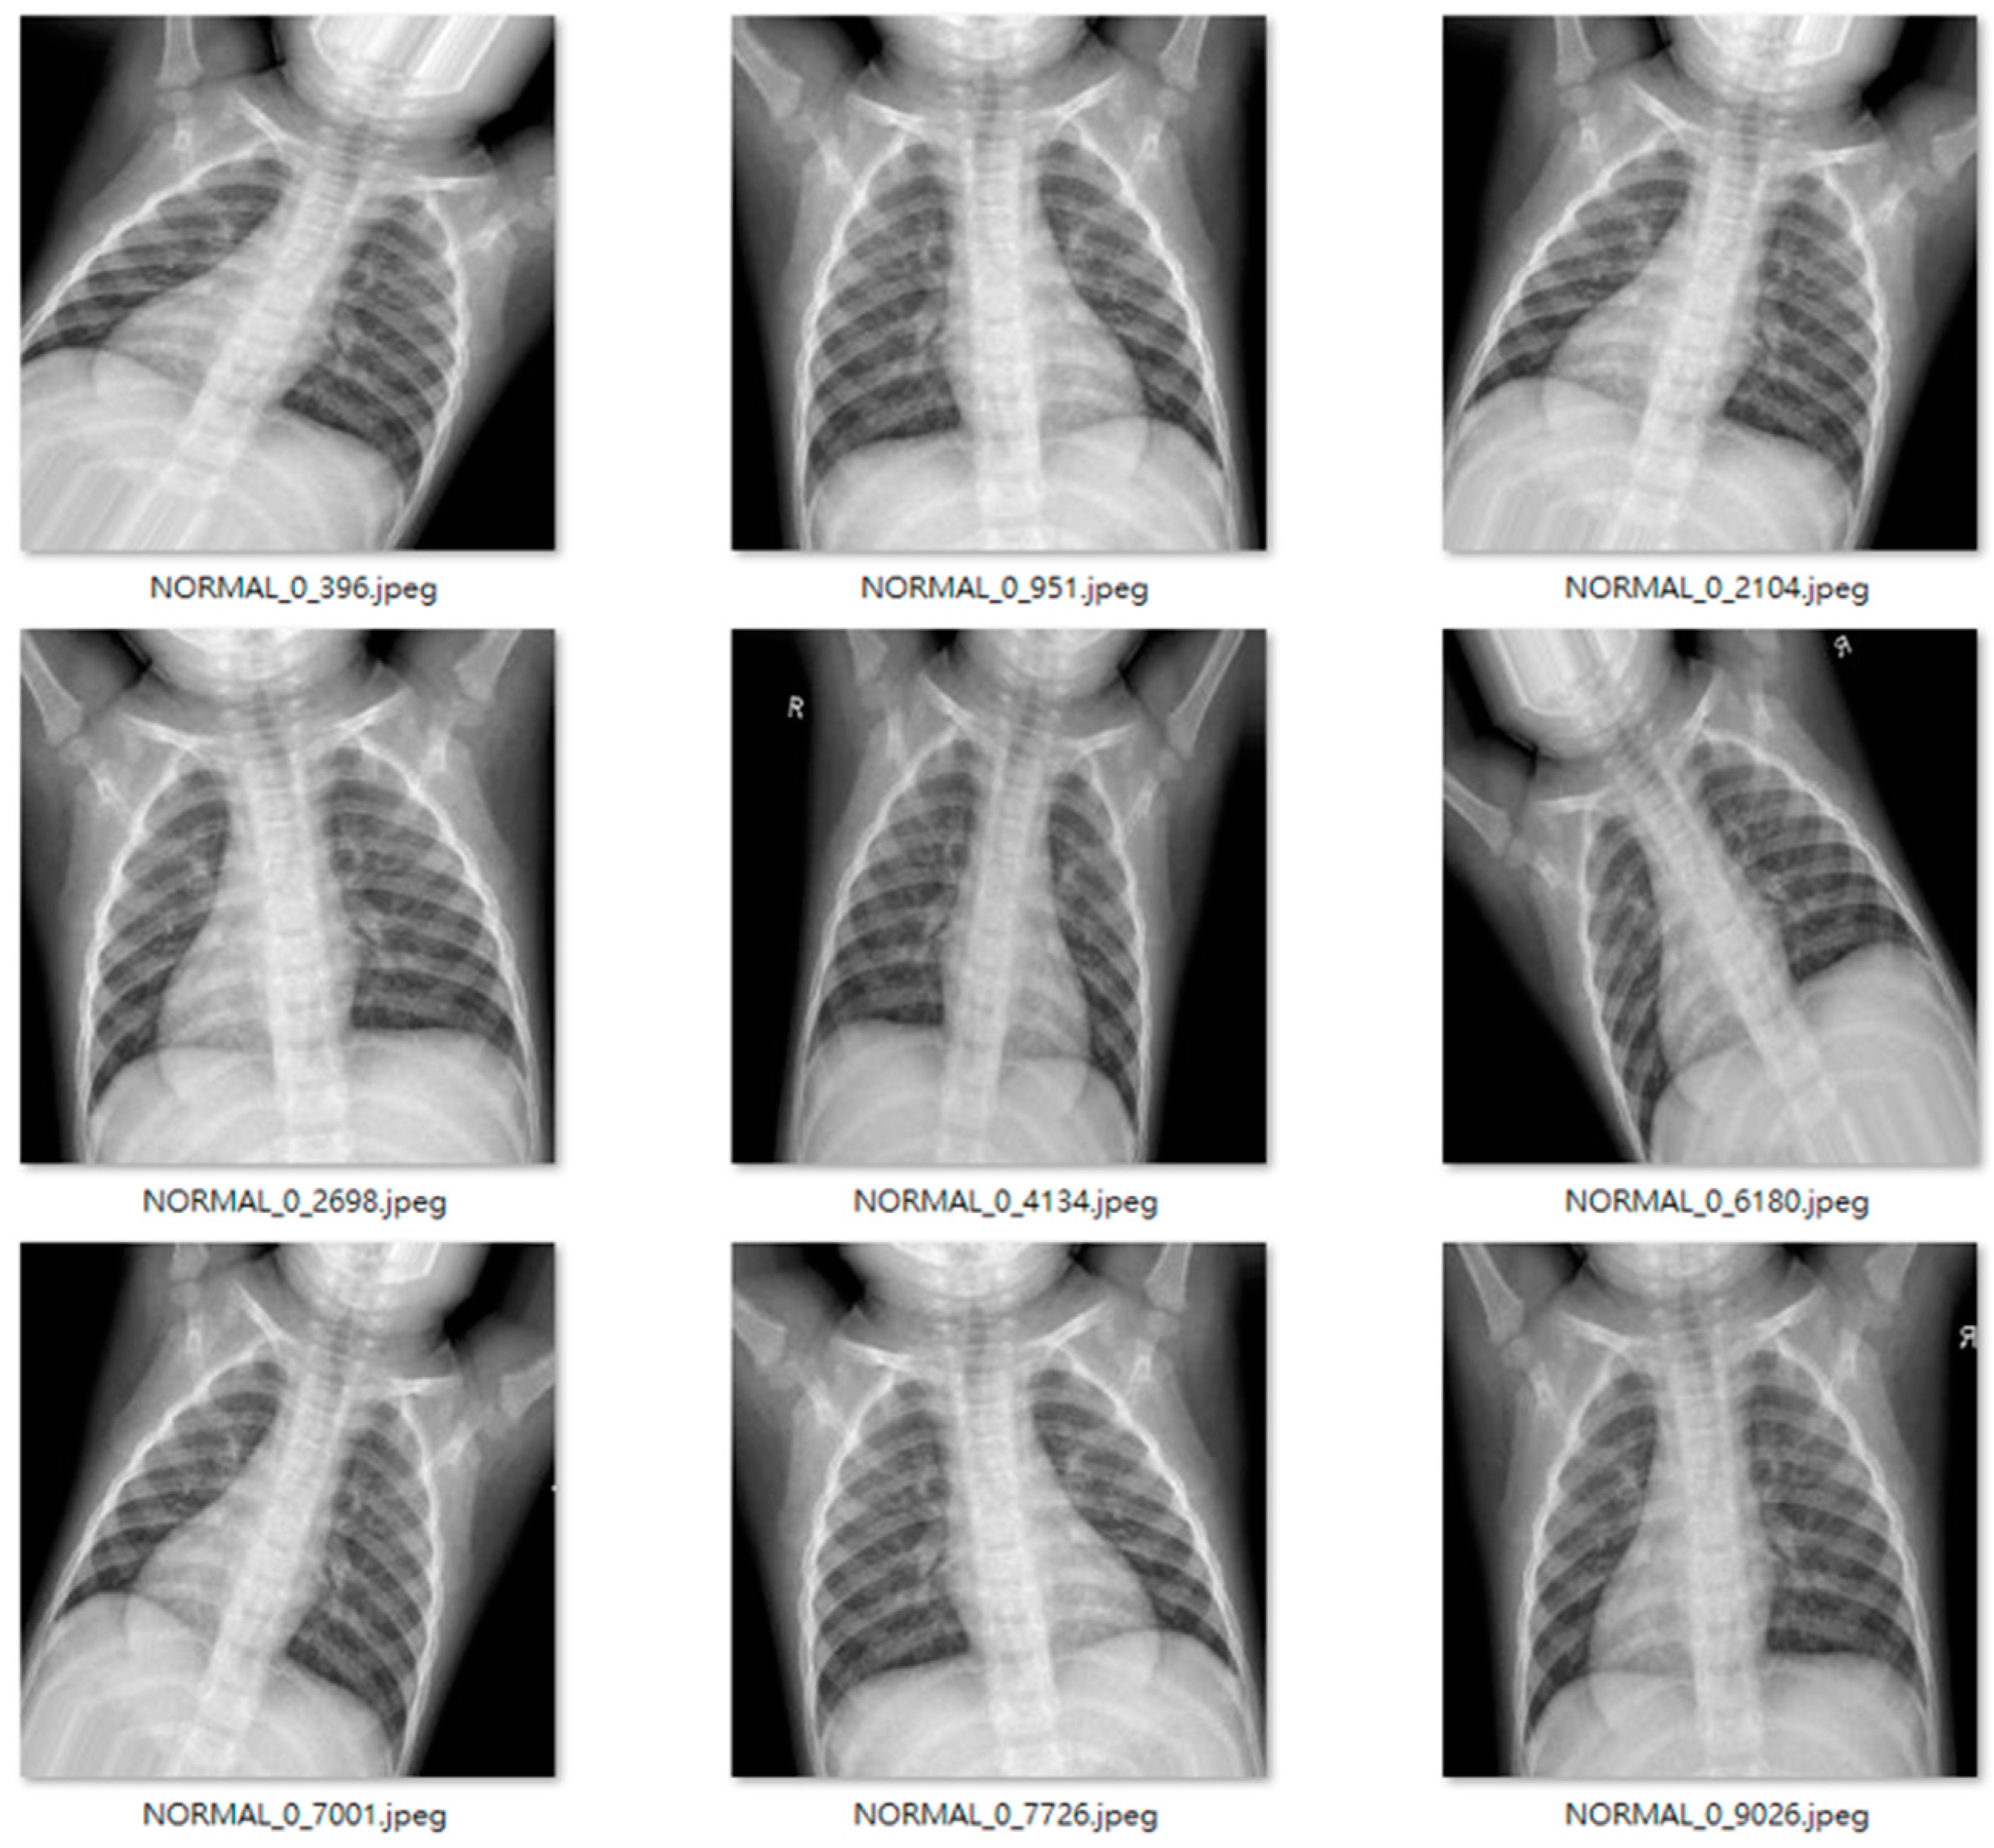

We used an open-source dataset provided by the Kaggle data science competition platform for training (https://www.kaggle.com/paultimothymooney/chest-xray-pneumonia accessed on 25 March 2018) [31]. The dataset comprised thoracic cavity images from child patients (1 to 5 years old) from the Guangzhou Women and Children’s Medical Center, China. These images were classified by two expert physicians and separated into training, test and validation sets. Figure 8 displays the dataset structure, with training sets including 1341 and 3875, test sets 234 and 390, validation set 8, and eight normal and pneumonia images, respectively. Figure 9 and Figure 10 show examples of normal and pneumonia thoracic cavity X-ray images, respectively.

Figure 9. Example normal thoracic cavity X-ray images from the study dataset [31].